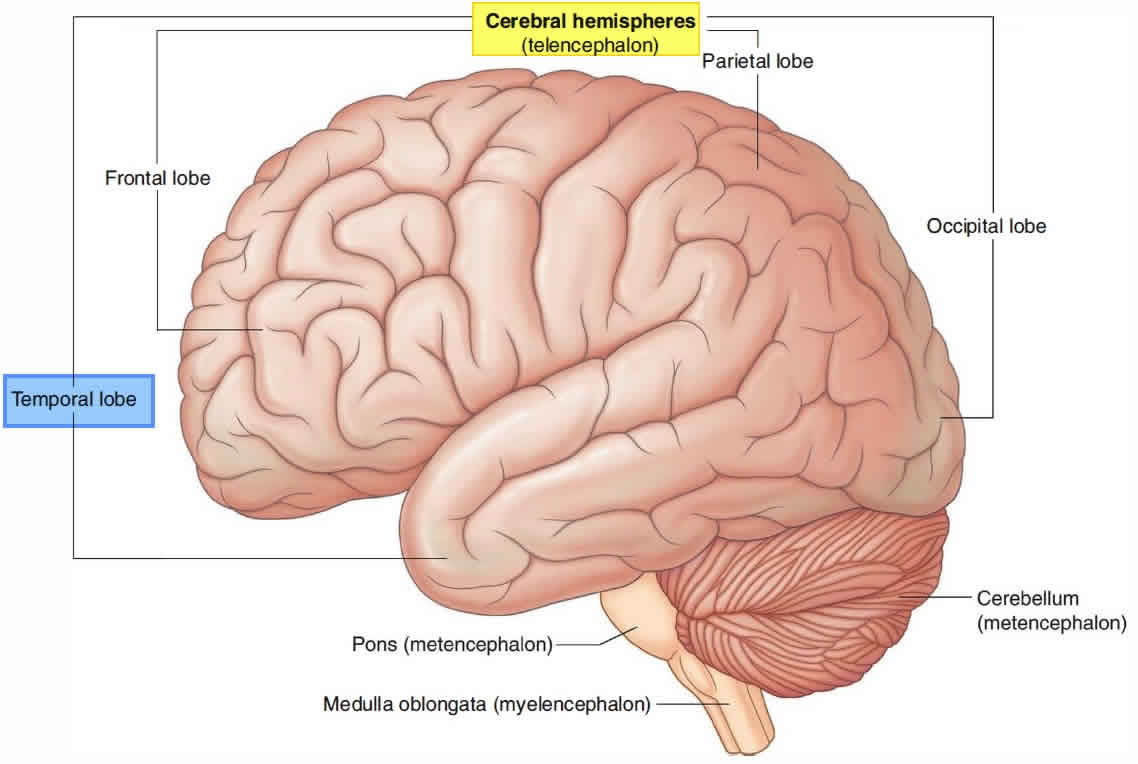

What Is Temporal Lobe

What Is Temporal Lobe

Temporal Lobe Anatomy Location Function Damage Epilepsy

Temporal Lobe Function Anatomy Info

Temporal Lobe SpinalCord

Temporal Lobe SpinalCord

Temporal Lobe The Definitive Guide Biology Dictionary

Temporal Lobe Function Location And Structure

Temporal Lobe

Temporal Lobe What Is It Location Structure Functions Injuries

Temporal Lobe What Is It Location Structure Functions Injuries